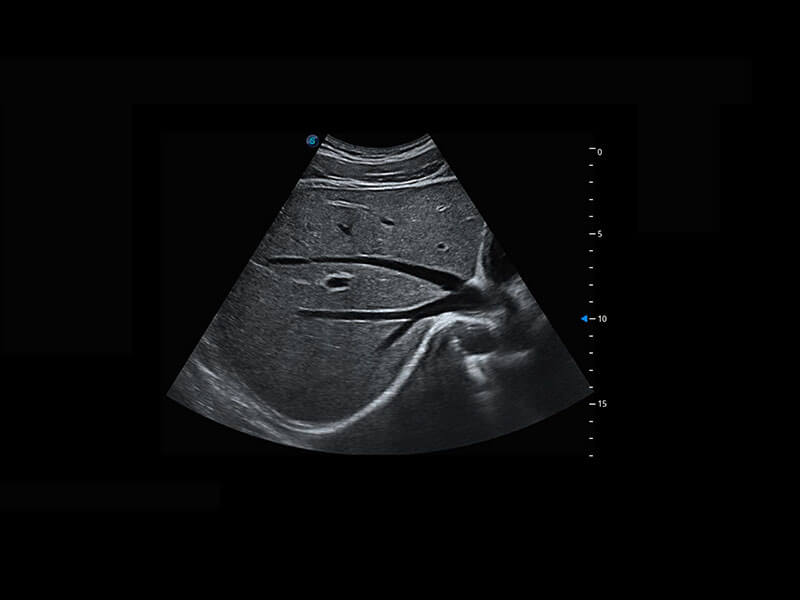

生殖健康

P60卓越的图像质量搭载专科探头,在妇科基础疾病的诊断、卵泡生长的监测、输卵管通畅情况的判别等方面为您提供全面的生殖应用方案。

• 腔内妇科-宫腔分离

• 腔内妇科-卵巢

• 腔内三维-宫内节育器

• 腔内三维-光影成像